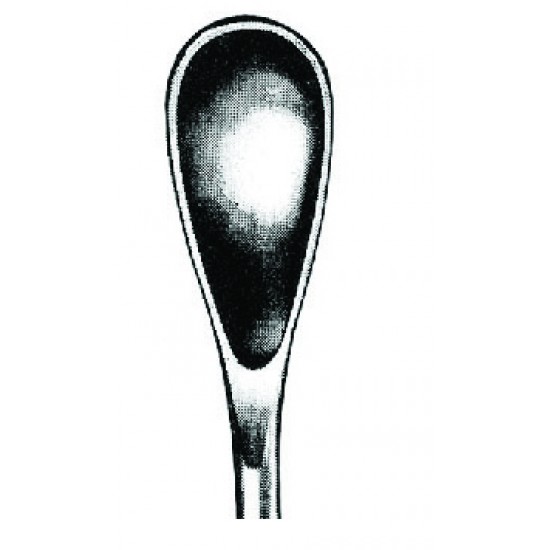

Uterine Scoops, Grourdet, 28.0 cm

- Model: 4U 29-8224-05